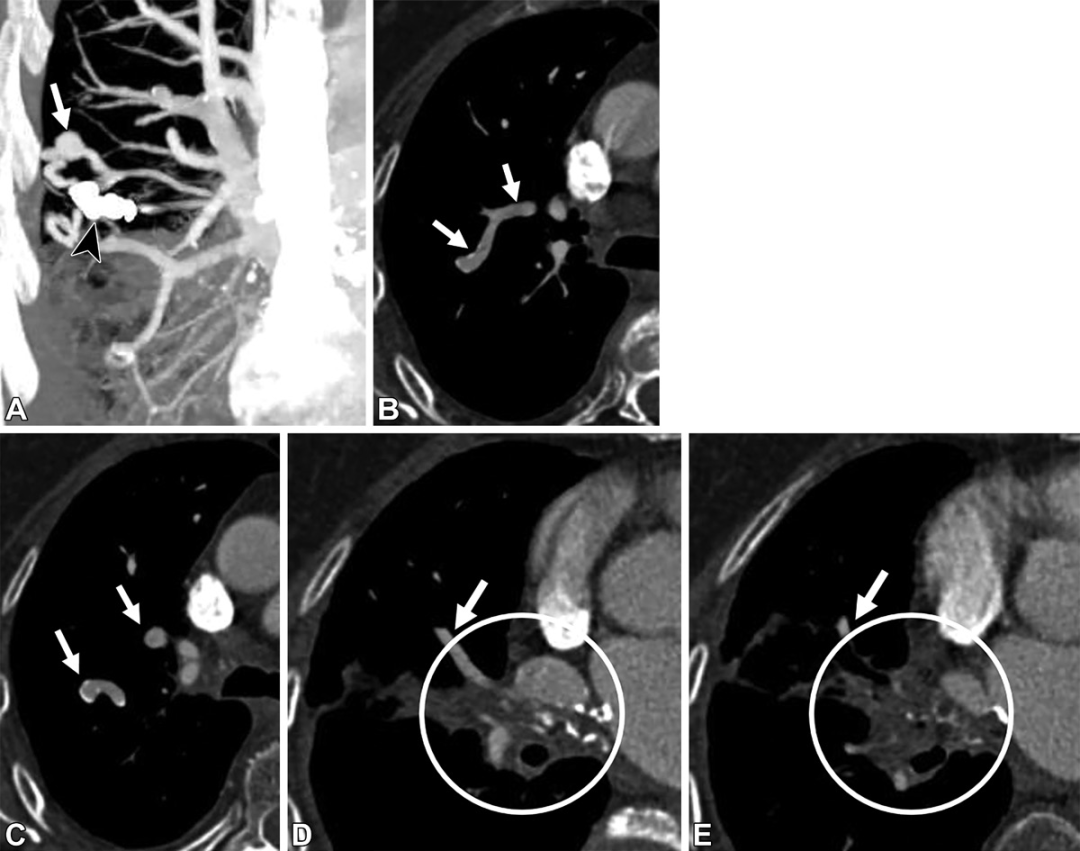

静脉静脉侧枝血管。39岁女性,8年前PAVM治疗史。(A)冠状位CT的最大密度投影图,可见右肺上叶血管内的弹簧圈(黑色短箭头),以及邻近的粗大血管结构(白色箭头)。(B至E)轴位CT图,可见扩张的静脉结构(白色箭头),但没有病灶或供血动脉。右肺门可见软组织增厚及钙化(白色圆圈),累及了静脉血管及支气管,符合纤维性纵膈炎表现。右上中肺静脉的阻塞会导致静脉结构扩张,称为静脉静脉侧枝血管。